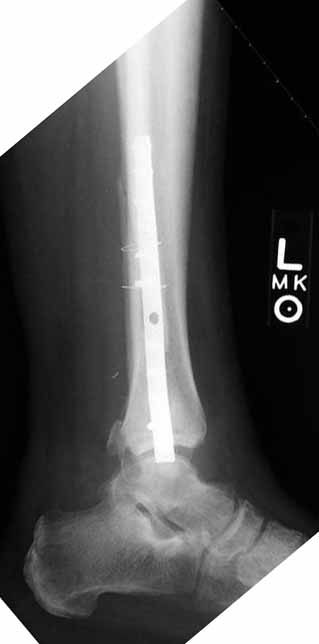

I would approach this problem by exposing medial, and reducing the talus to the medial side- hold it with a pin. I would then address lateral, and do whatever it took to reposition the fibula as others have stated so well. My personal preference for syndesmosis reconstruction is two medium barbed staples that parallel the ant tib-fib ligament (referenced in Kelikian's book on the ankle) +/- a ligament weave to try and reconstitute the tib-fib ligament. The staples stay in for good, and are more reliable than screws in my anecdotal experience. See attachments below. Patient presented after 3 attempts to squeeze the mortise down. Fibular shortening and malrotation present. Rx with lengthening and derotation + staple fixation of the syndesmosis.

James B. Carr, MD

Palmetto Health Orthopedics